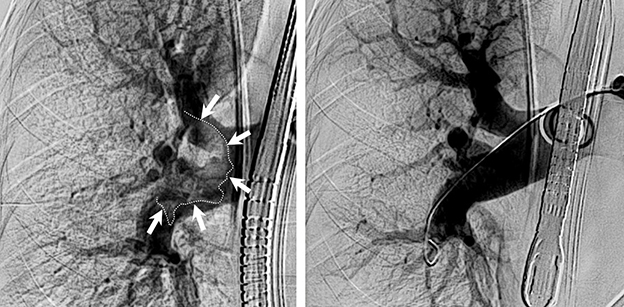

Im Bild: Lunge mit großem Blutgerinnsel (markiert) und dementsprechend mangelnder Durchblutung (links) und nach Entfernung des Gerinnsels und guter Durchblutung (rechts).